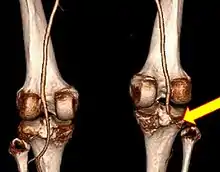

Plain X-rays, CT scan, ultrasonography, or MRI may help with the diagnosis.[2][11] Findings on X-ray that may be useful among those who have already reduced include a variable joint space, subluxation of the joint, or a Segond fracture.[5]

They may be divided into five types: anterior, posterior, lateral, medial, and rotatory.[4] This classification is based on the movement of the tibia with respect to the femur.[11] Anterior dislocations, followed by posterior, are the most common.[2] They may also be classified on the basis of which ligaments are injured.[2]